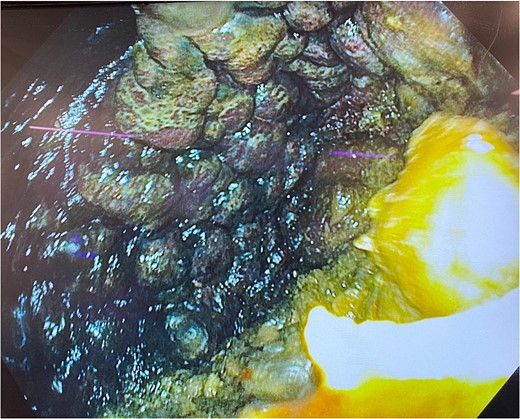

He was expedited to theatre, commencing with gastroscopy to exclude an intraluminal mechanical obstruction. There was widespread mucosal ulceration and necrosis (Figs 4–7) necessitating a laparotomy and assessment for transmural necrosis. The stomach was globally ischaemic with gangrene at the fundus (Figs 8–10) and hence a total gastrectomy was performed and reconstructed with roux-en-y oesophagojejunostomy and jejunojejunostomy.

Gastroscopy showing multiple areas of mucosal ulceration and ischaemia.